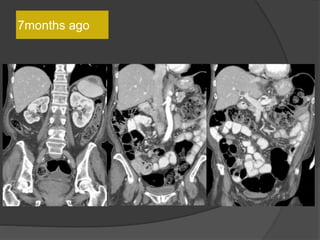

7months ago

10 months ago

Case 1: 64F, abdominal distention, pain, h/o

SBO

• Multilobulated thick-walled cystic lesion in the lesser sac and extending along the

adjacent peritoneal spaces and gastrohepatic ligament. Cystic lesion in the left

hemipelvis

• Minimal ascites, omental and mesenteric thickening

Present exam 15 days ago

Increased size

15 days

ago

Present exam

Case 1 Diagnosis: Recurrent metastatic disease

with mucinous ovarian tumor